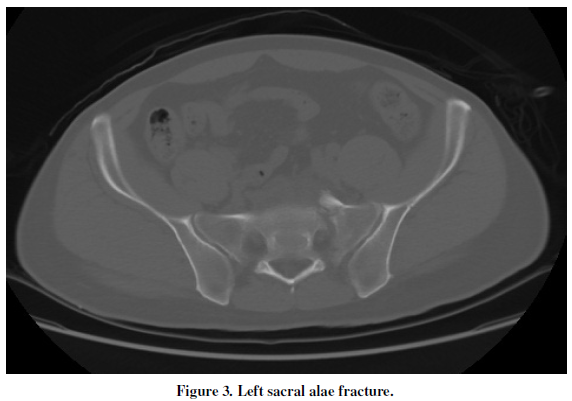

The 44-year-old male with hypertension and diabetic presented in the emergency department with torso pain after motor vehicle crash 30 minutes ago. The pain was located at right upper quadrant, flank, chest and back. Vital signs were stable. The sonography showed ascites over Morison’s pouch. The laboratory data showed GOT of 462 U/L and GPT of 497 U/L. The results of contrast-enhanced computed tomography (CT) were as following: (1) right adrenal gland hematoma with contrast extravasation(Figure 1, Figure 2), (2) liver laceration Grade II (Figure 1),(3) pelvic fracture (Figure 3). He received conservative treatment and discharged smoothly 20 days later.

Traumatic adrenal injury is a relative rare event which is reported in 0.15 to 4% of the blunt abdominal trauma cases[1]. Adrenal trauma is unilateral in 75–90 % of cases and most commonly affects the right adrenal gland [2]. The clinical management of adrenal trauma is usually directed by concomitant injuries, while the adrenal trauma itself is most often managed conservatively [3]. In addition, the most common CT manifestation of adrenal trauma is 2–3-cm oval hematoma [2]. Finally, the adrenal injury is an important indicator of the severity of trauma and associated with increased morbidity and mortality [2], such as in this case.